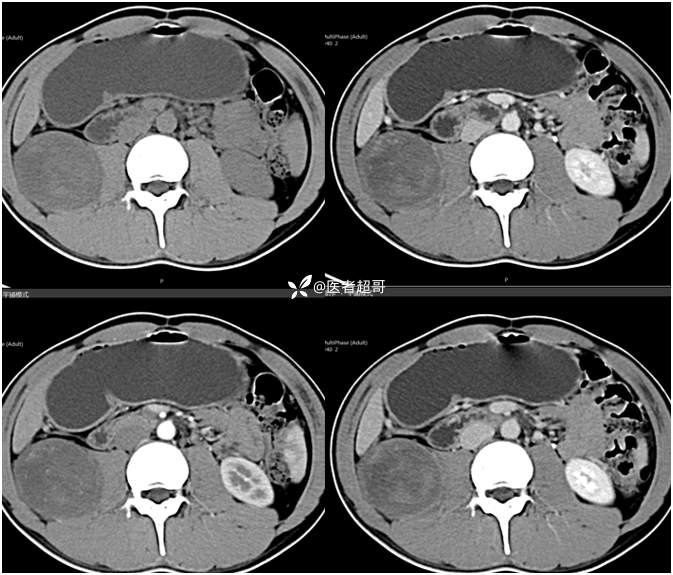

【影诊笔记754】腰痛就诊,腹膜后实性占位,请诊断分析!

主 诉:腰痛2月。

现病史:患者2月前无明显诱因出现腰背部疼痛,夜间为著。患者无头痛、头晕,无恶心、呕吐,无胸闷、憋气,无腹痛、腹胀。无尿频、尿急、尿痛等现象。患者在院外未作特殊治疗。为求进一步诊疗,来我院肾内科门诊就诊。门诊行双肾、输尿管、膀胱(前列腺)彩超提示:腹膜后实性占位。患者遂来我科就诊。我科以“腰痛”收治入院,患者自发病以来,神志清,精神可,饮食可,睡眠差。小便如上述,大便未见明显异常。体重无明显增减。